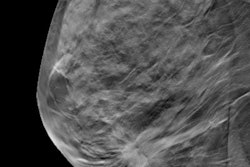

- Read why researchers believe digital breast tomosynthesis (DBT) could change the screening equation for younger women.

- Discover why fewer women with a history of breast cancer get necessary mammography screening.

- Learn more about the Dartmouth College investigation that found that Dr. H. Gilbert Welch plagiarized material from a colleague in a 2016 New England Journal of Medicine study about overdiagnosis in screening mammography.

- Find out why Australian researchers say DBT's benefits vary between Europe and the U.S.